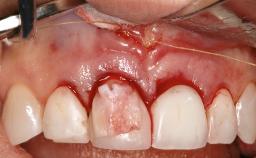

Treatment of Peri-Implant Mucositis at a Zirconia Implant